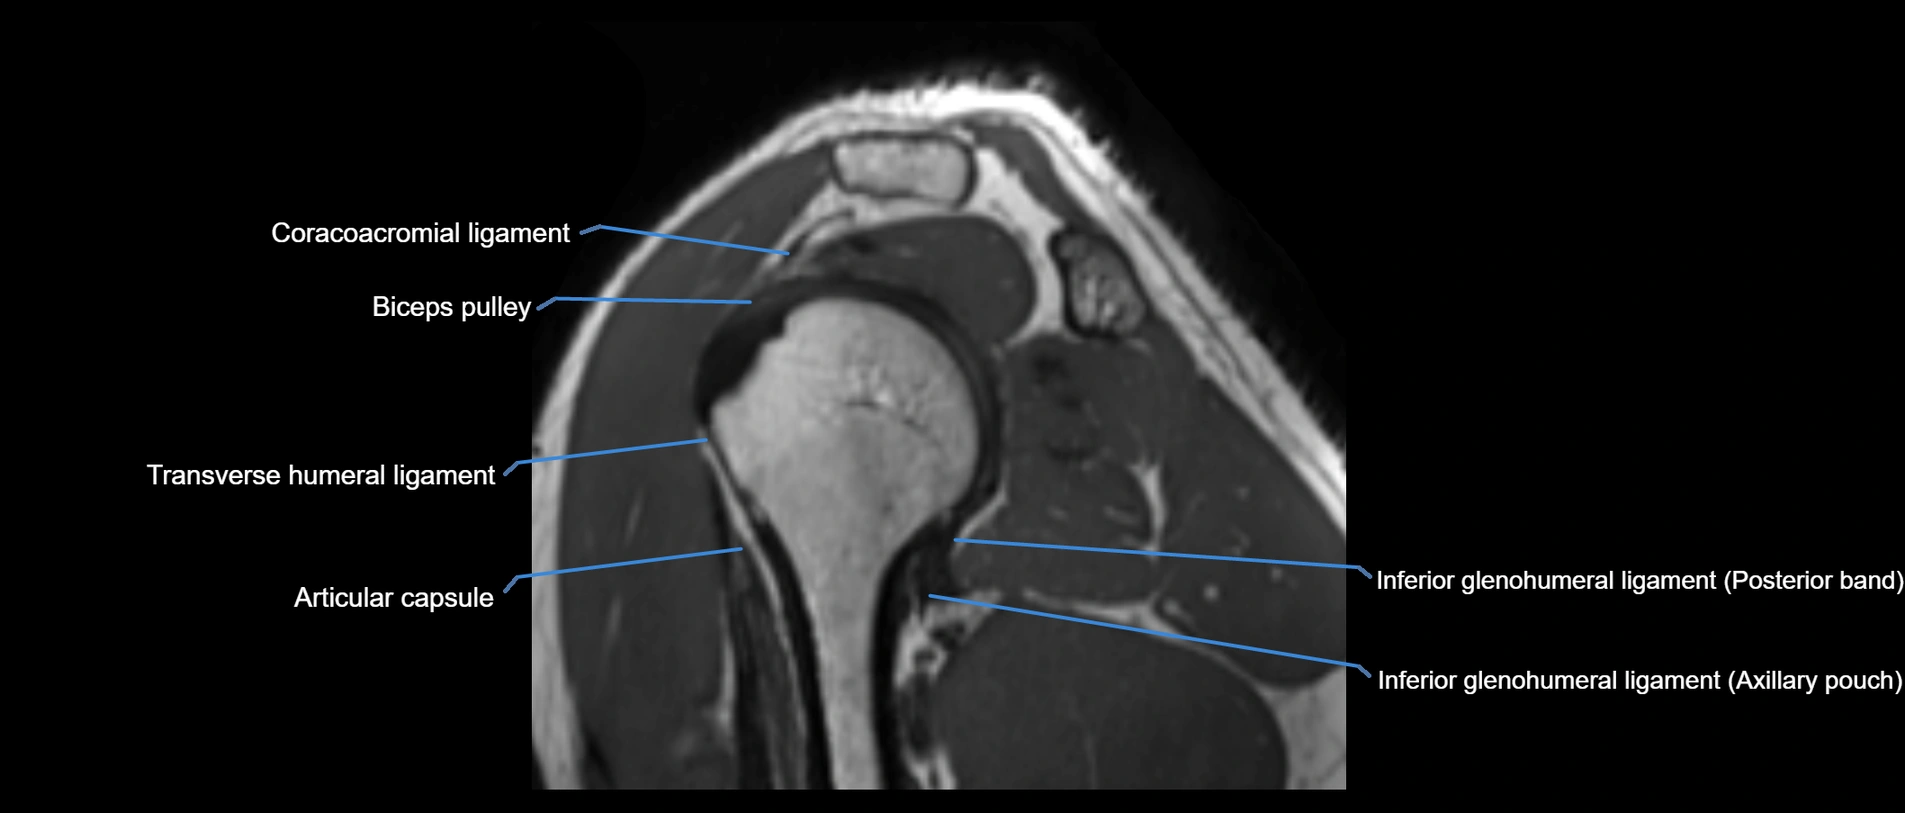

MRI images

image